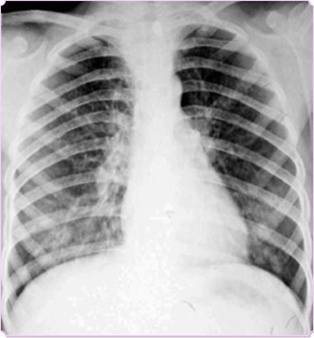

圖中可見右上葉“斑點花”,根據公式診斷為小葉性肺炎